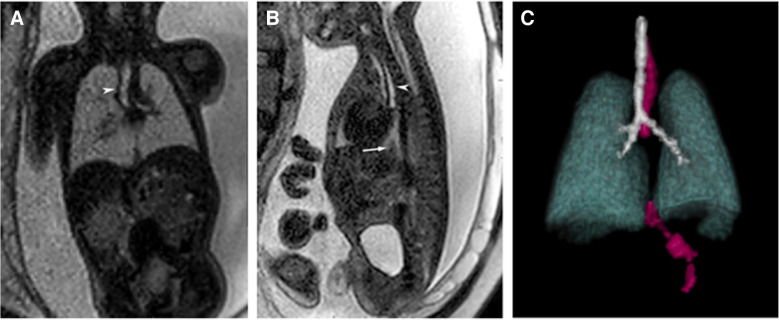

背景:食管闭锁的产前诊断仍然具有挑战性,羊水过多、胃泡小或不存在、食管上袋扩张等间接体征经常不一致地出现。只有10-40%的EA病例是产前诊断出来的。胎儿MRI可以克服超声的限制;然而,运动等限制因素会阻碍对食道的评估。方法:采用切片-体积重构(SVR)技术进行超分辨率成像是提高图像质量的一种方法。该技术从标准的胎儿MRI切片生成高分辨率3D图像,以提高诊断准确性。目的:应用SVR超分辨率成像技术对气管食管瘘进行准确诊断和诊断。结论:该技术在准确描绘相关手术解剖结构方面具有重要潜力,可改善手术计划。

Background: Prenatal diagnosis of esophageal atresia remains challenging, with indirect signs such as polyhydramnios, a small or absent stomach bubble, and a dilated upper esophageal pouch often inconsistently present. Only 10-40% of EA cases are diagnosed prenatally. Fetal MRI can overcome ultrasound limitations; however, constraints like motion can hinder evaluation of the esophagus.

Methods: Super-resolution imaging with slice-to-volume reconstruction (SVR) is one approach that can improve image quality. This technique generates high-resolution 3D images from standard fetal MRI slices to enhance diagnostic accuracy.

Aim: We present the application of super-resolution imaging with SVR to accurately diagnose EA and assess the presence or absence tracheoesophageal fistulas.

Conclusion: This technique demonstrates significant potential for accurately delineating the relevant surgical anatomy, which can improve surgical planning.